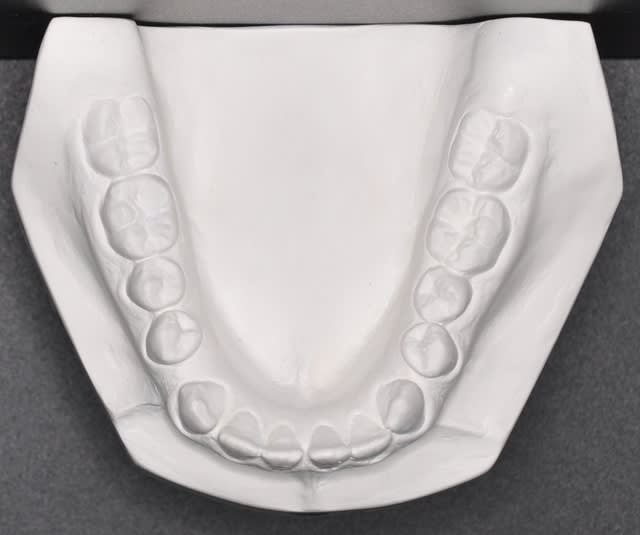

Saïd, je pense que nous devons faire confiance à Takamatika. C'est lui (elle ?) qui a fait l'examen clinique et positionné les modèles en plâtre.

oui mais Takamatika a mis les modèle en PIM et Saïd voudrait les voir en RC. Quel est le chemin de fermeture?

Personnellement dans un cas de lateromandibulie combinee (d'origine fonctionnelle, positionnelle et/ou squelettique) un montage sur articulateur devient indisponsable avec une radio de face afin d'estimer la dissymetrie mandibulaire.